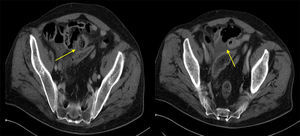

Varón de 67años con antecedentes de mesotelioma pleural maligno (T3N2M0) intervenido en julio 2010, en el que se realizó una pleuroneumectomía radical con linfadenectomía, recibiendo quimioterapia adyuvante y en seguimiento por Oncología. Acude a Urgencias en agosto de 2011 por dolor abdominal de 4h de evolución, de inicio súbito, localizado en el hipogastrio y que posteriormente se hace difuso. A la exploración presenta abdomen con defensa generalizada y signos de irritación peritoneal. La analítica está dentro de los límites de la normalidad. La radiografía de abdomen no presenta hallazgos relevantes y se realiza una TC abdominal con contraste intravenoso que informa de neumoperitoneo, engrosamiento mural circunferencial de un corto segmento de intestino delgado en hipogastrio (yeyuno) con marcados cambios inflamatorios y pequeñas burbujas de aire adyacente (fig. 1). Ante los hallazgos se decide intervención quirúrgica urgente mediante laparotomía media supra-infraumbilical, hallando peritonitis aguda purulenta inframesocólica por perforación única de yeyuno sobre placa isquémica. Se realiza resección intestinal y anastomosis término-terminal manual. El postoperatorio fue satisfactorio, y la anatomía patológica informa de metástasis de mesotelioma maligno epitelioide en la pared intestinal y en 2 ganglios aislados. El paciente fue remitido a Oncología, iniciando tratamiento con quimioterapia.